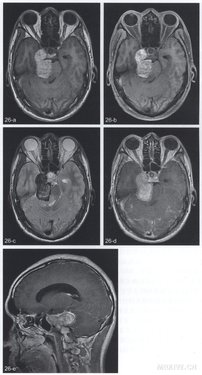

T1WI(图26a)显示右侧鞍旁花生状肿物,呈欠均匀高信号,最大径4.lcm,边缘清楚,向颅后窝延伸、压迫脑桥前缘,右侧颈内动脉海绵窦段及Meckel腔显示不清。上述肿物脂肪抑制序列上信号未见降低(图26b)。T2WI上肿物为低信号,周边部为著,内部有斑片状稍高信号,肿物后方脑桥内少许稍长T2信号的水肿(图26c)。增强扫描肿物后部见轻度斑片状强化,脑桥内稍长T2信号区未见增强(图26d,e)。

【手术后病理诊断】

CT特点为肿瘤呈平扫境界清楚的高密度肿块,也可为等或略高密度,高密度者增强扫描无强化,等及稍高密度肿块则明显及均匀强化。MRI特点与黑色素颗粒多少有关,黑色素颗粒越多则T1WI信号越高、T2WI信号越低,增强扫描无强化或轻度强化。这种特征性信号改变的原因是黑色素内顺磁性自由基如半醌等所致的顺磁性效应,导致T1与T2弛豫时间缩短。也有作者提出肿瘤内出血造成T.弛豫时间缩短,但病理学检查证明大多数黑色素细胞瘤内并无出血。少数黑色素较少或几乎缺乏,为T1WI均匀等信号及T2WI高信号。